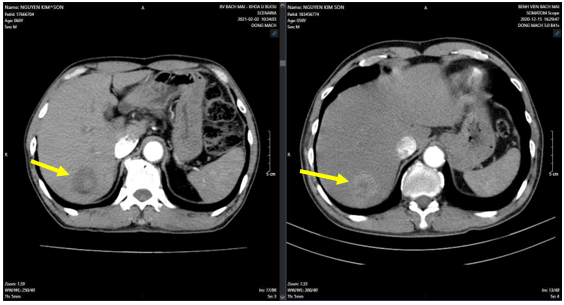

Hình 2: U gan sau SIRT (bên trái, mũi tên vàng) so với trước SIRT (bên phải, mũi tên vàng)

– Tháng 3/2025: Hình ảnh u phân thùy sau gan phải, kích thước 28x38mm, hiện còn tăng sinh mạch (Sau TACE lần 3). Sỏi túi mật. Sỏi thận hai bên.